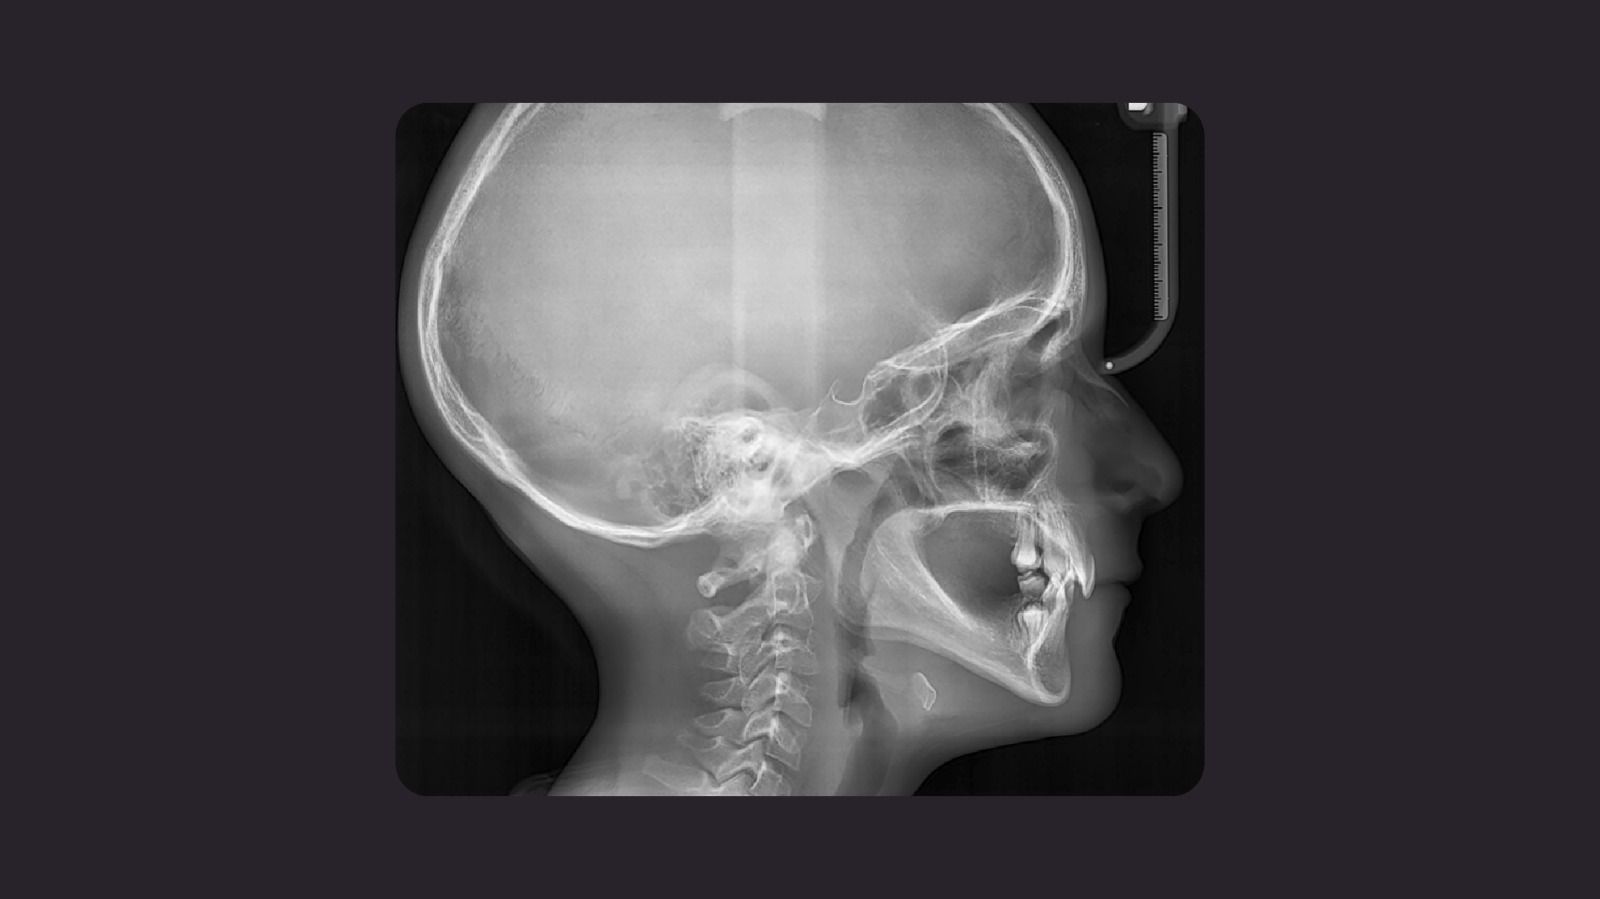

Figura 2

Fig.2: Radiografía Lateral. Se puede apreciar:

- Maxilares parcialmente atróficos.

- Pérdida de la dimensión vertical.

- Disminución del proceso alveolar en regiones edéntulas del maxilar superior e inferior.

- Crestas alveolares atróficas.